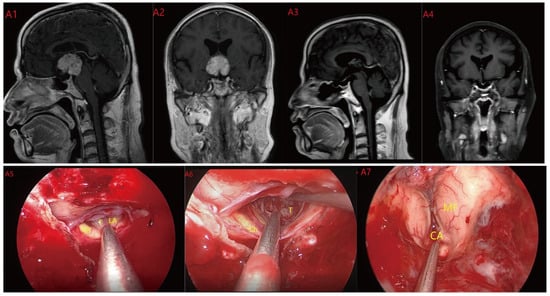

Figure 4.

Case 4 Type III: the tumor grows strictly inside the third ventricle. (A1,A2) The TLTA was used; the pituitary stalk could not be seen during the surgery (A5–A7). Finally, the tumor was totally resected (A3,A4). Optic chiasm (Ch), foramen of Monroe (MF), massa intermedia (MI), cerebral aqueduct (CA), tumor (T).